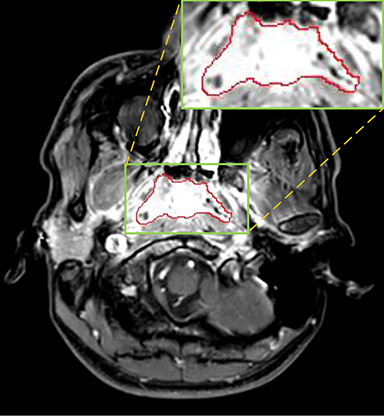

Currently, there is still no effort to fuse multi-modality MRI to develop an automatic segmentation system for NPC. According to researches of Popovtzer et al. [16], it should be a routine clinical practice to incorporate all kinds of MRI datasets in highly conformal radiation therapy to realize GTV delineation of NPC. For delineation of NPC, MRI is the perferred imaging modality for its superior soft tissue contrast [16, 3]. Moreover, MRI of different modalities data have different visual characteristics and various responses to different tissues and anatomical structures. For example, T1-weighted (T1) MRI is suitable for detecting skull base involvement and fat planes, while contrast-enhanced T1-weighted (CET1) MRI is used to identity tumor extent [3]. Figure 1 shows some examples of NPC response in T1, CET1 and T2-weighted (T2) MRI.

Comparison with ground truth. Some predicted results of MMFNet are shown in 2D images and 3D images in Figure 7 and Figure 8. As shown in these figures, although the shape and size of NPC are varied from each other, MMFNet can still accurately determine the regions of NPC and obtain the accurate contours of tumors. Through analyzing 2D images in figure 7, MMFNet has a capacity to fuse multi-modality MRI to reduce the confusion brought by intensity’ similarity between nearby tissues and NPC. The values of , and of MMFNet are shown in Table 1. MMFNet can reach the best results with , and .